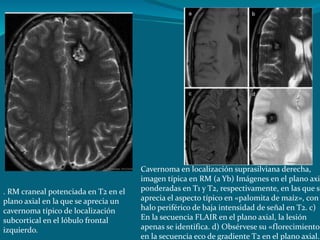

. RM craneal potenciada en T2 en el

plano axial en la que se aprecia un

cavernoma típico de localización

subcortical en el lóbulo frontal

izquierdo.

Cavernoma en localización suprasilviana derecha,

imagen típica en RM (a Yb) Imágenes en el plano axia

ponderadas en T1 y T2, respectivamente, en las que se

aprecia el aspecto típico en «palomita de maíz», con

halo periférico de baja intensidad de señal en T2. c)

En la secuencia FLAIR en el plano axial, la lesión

apenas se identifica. d) Obsérvese su «florecimiento»

en la secuencia eco de gradiente T2 en el plano axial.